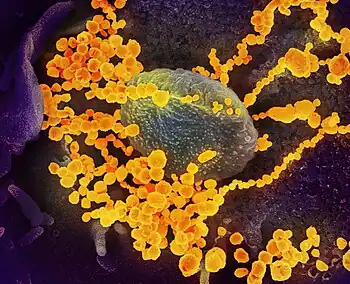

Photo credit: Public domain (U.S. Brookhaven National Laboratory)